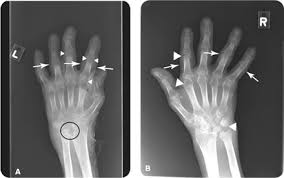

If the pattern of disease is not symmetrical, then a different diagnosis should be considered. Imaging tests you may get. The 2010 rheumatoid arthritis classification criteria help doctors diagnose rheumatoid arthritis. The ulnar styloid is destroyed with the rest of the distal ulna (white arrow), there is destruction of the carpal bones (yellow arrow) and there is dislocation of the 1st metacarpal on the destroyed trapezium. It can affect anyone of any age. Rheumatoid arthritis (ra) is a chronic autoimmune multisystemic inflammatory disease that affects many organs but predominantly attacks the synovial tissues and joints. Rheumatoid arthritis affects around 400,000 adults aged 16 and over in the uk. Rheumatoid arthritis can be difficult to diagnose because many conditions cause joint stiffness and inflammation and there's no definitive test for the condition. Ra causes pain, swelling, stiffness, and loss of function in joints. Rheumatoid arthritis is an inflammatory arthritis affecting both small and large joints in a symmetric distribution. Rheumatoid arthritis is an immune system condition, or autoimmune disorder, that causes inflammation of the lining of the joints. Rheumatoid arthritis is a chronic inflammatory disorder that can affect more than just your joints. Rheumatoid arthritis manifests as a symmetrical arthritis, most commonly affecting the hands.

If the pattern of disease is not symmetrical, then a different diagnosis should be considered. In rheumatoid arthritis, the body's immune system attacks its own healthy cells inside certain joints, leading to an inflammatory response. For more information and past images of the month, go to. However, they are not useful in the early stages of rheumatoid arthritis, before joint damage occurs. </b>rheumatoid arthritis (ra) is a polyarticular disease with bilateral and symmetric distribution. Sorptiometry should be performed to diagnose. The rheumatoid community on reddit. Rheumatoid arthritis (present for >10 years). The ulnar styloid is destroyed with the rest of the distal ulna (white arrow), there is destruction of the carpal bones (yellow arrow) and there is dislocation of the 1st metacarpal on the destroyed trapezium. Rheumatoid arthritis affects around 400,000 adults aged 16 and over in the uk. Reddit gives you the best of the internet in one place. Ra causes pain, swelling, stiffness, and loss of function in joints. The earliest manifestation of rheumatoid arthritis of the forefoot is synovitis of the mtp joints with eventual hyperextension deformity of the mtp joints including distal.